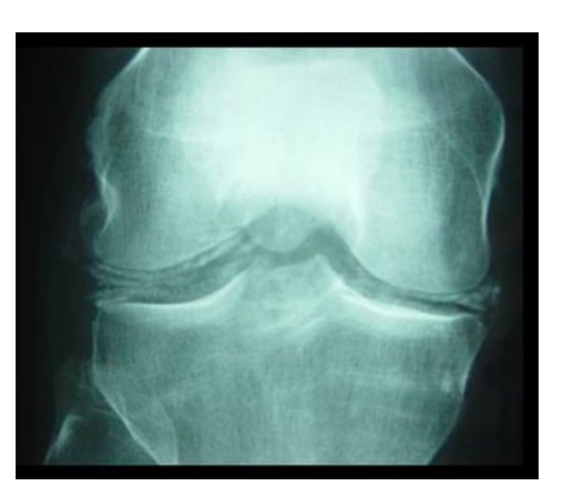

Chondrocalcinose articulaire

calcif linéaires des ménisques